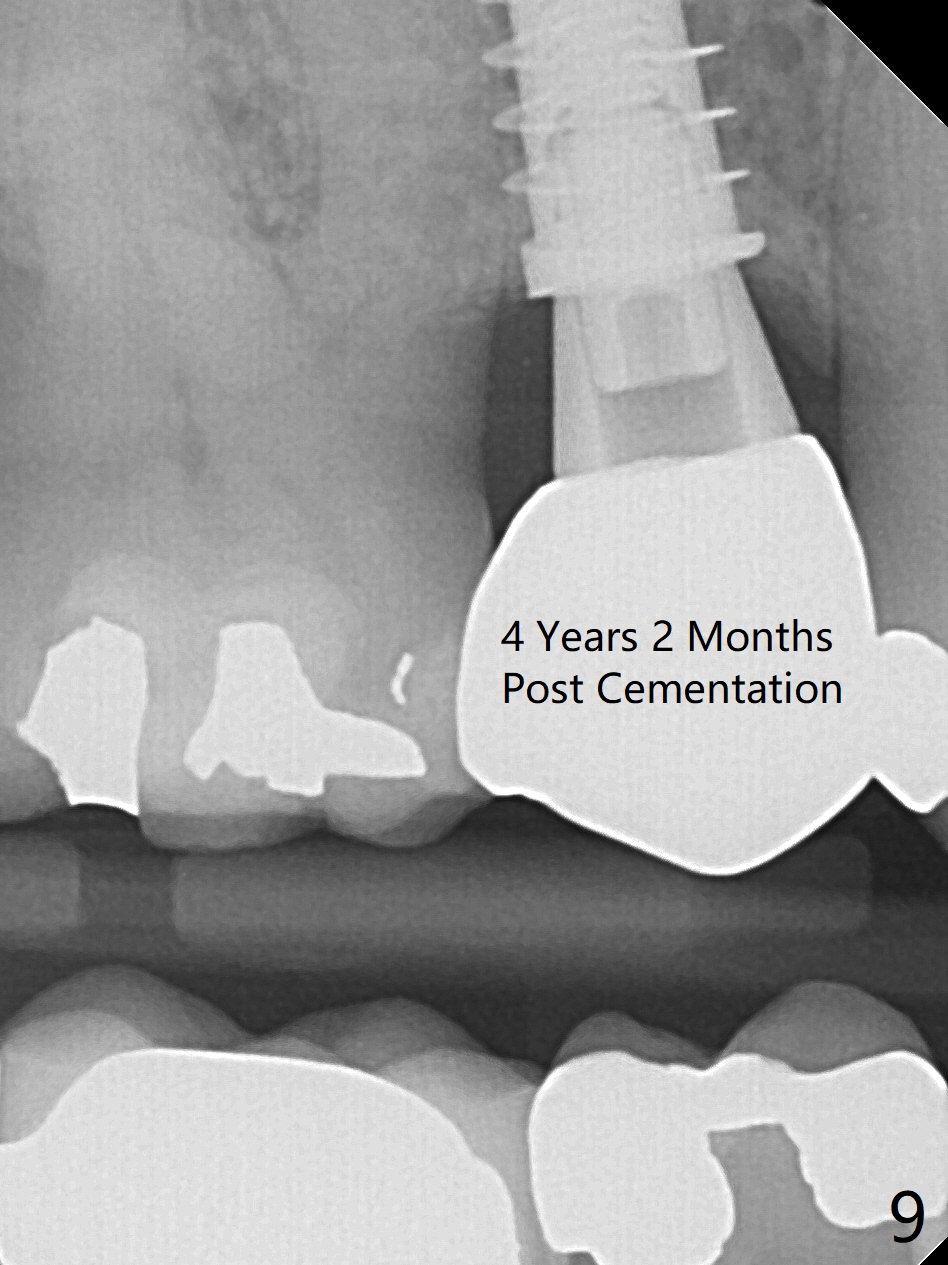

To prevent sinus lift related sinusitis, a shorter implant is going to be placed (Fig.1), approximately 2 mm beyond the apex.  Following extraction, the buccal plate (Fig.3a (coronal section): B) is not only ~ 2 mm shorter than the palatal one (P), but also thinner.  Since the bone density of the palatal plate is higher, without osteotomy an implant is less likely placed in the middle of the socket (S (Fig.1); Fig.3b) than buccal (Fig.3c).  Therefore drills are used to form osteotomy in the apical 1/3 of the palatal slope (Fig.3d (red arrow); SM: sinus membrane).  When 3.3 mm Magic Drill (MD) is in place (Fig.2), the distal surface of the sinus septum is perforated without air leakage.  Demineralized allograft (.0125-.085) is placed for sinus lift (Fig.4 *) prior to placement of 4.5x11 mm implant with ~ 30 Ncm.  The implant is slightly buccal to the ideal position indicated in Fig.3e (curved blue line: sinus lift).  A 4.5x4(2) mm pair abutment is placed for an immediate provisional to hold mineralized allograft in the remaining socket gaps (Fig.4 arrowheads, .5-1.5 mm).  A 9 mm implant may avoid sinus floor perforation on the distal slope of the 2nd premolar.  The osteotomy should have been established initially as mesial as possible.  In fact the patient has nasal hemorrhage while sneezing for the first 2 days postop.  Although he complains of pain buccal to the implant, the gingiva appears to heal 7 days postop (Fig.5).  The distobuccal papilla appears to be displaced somewhat.  Raising mucoperiosteal flap is most likely associated with postop pain and esthetic compromise.  The implant appears to have osteointegrated 5 months postop (Fig.6).  A 4.5 mmx15° 3 mm cuff angled abutment is placed for final restoration.  The distolingual portion of the implant is supported by the regenerated bone 3 years post cementation (Fig.7,8).  There is no bone loss 4 years 2 months post cementation (Fig.9,10).